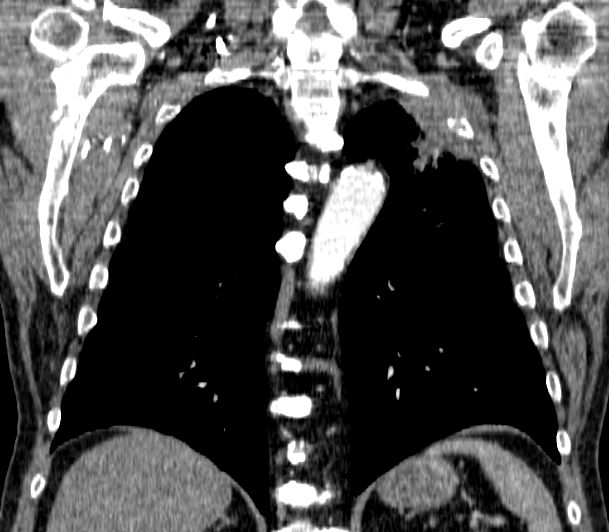

| Thoraxwanddestruktion | Plattenepithelkarzinom des rechten

Lungenoberlappens mit Destruktion der Thoraxwand und mediastinalen

Lymphknotenmetastasen. ![]() |